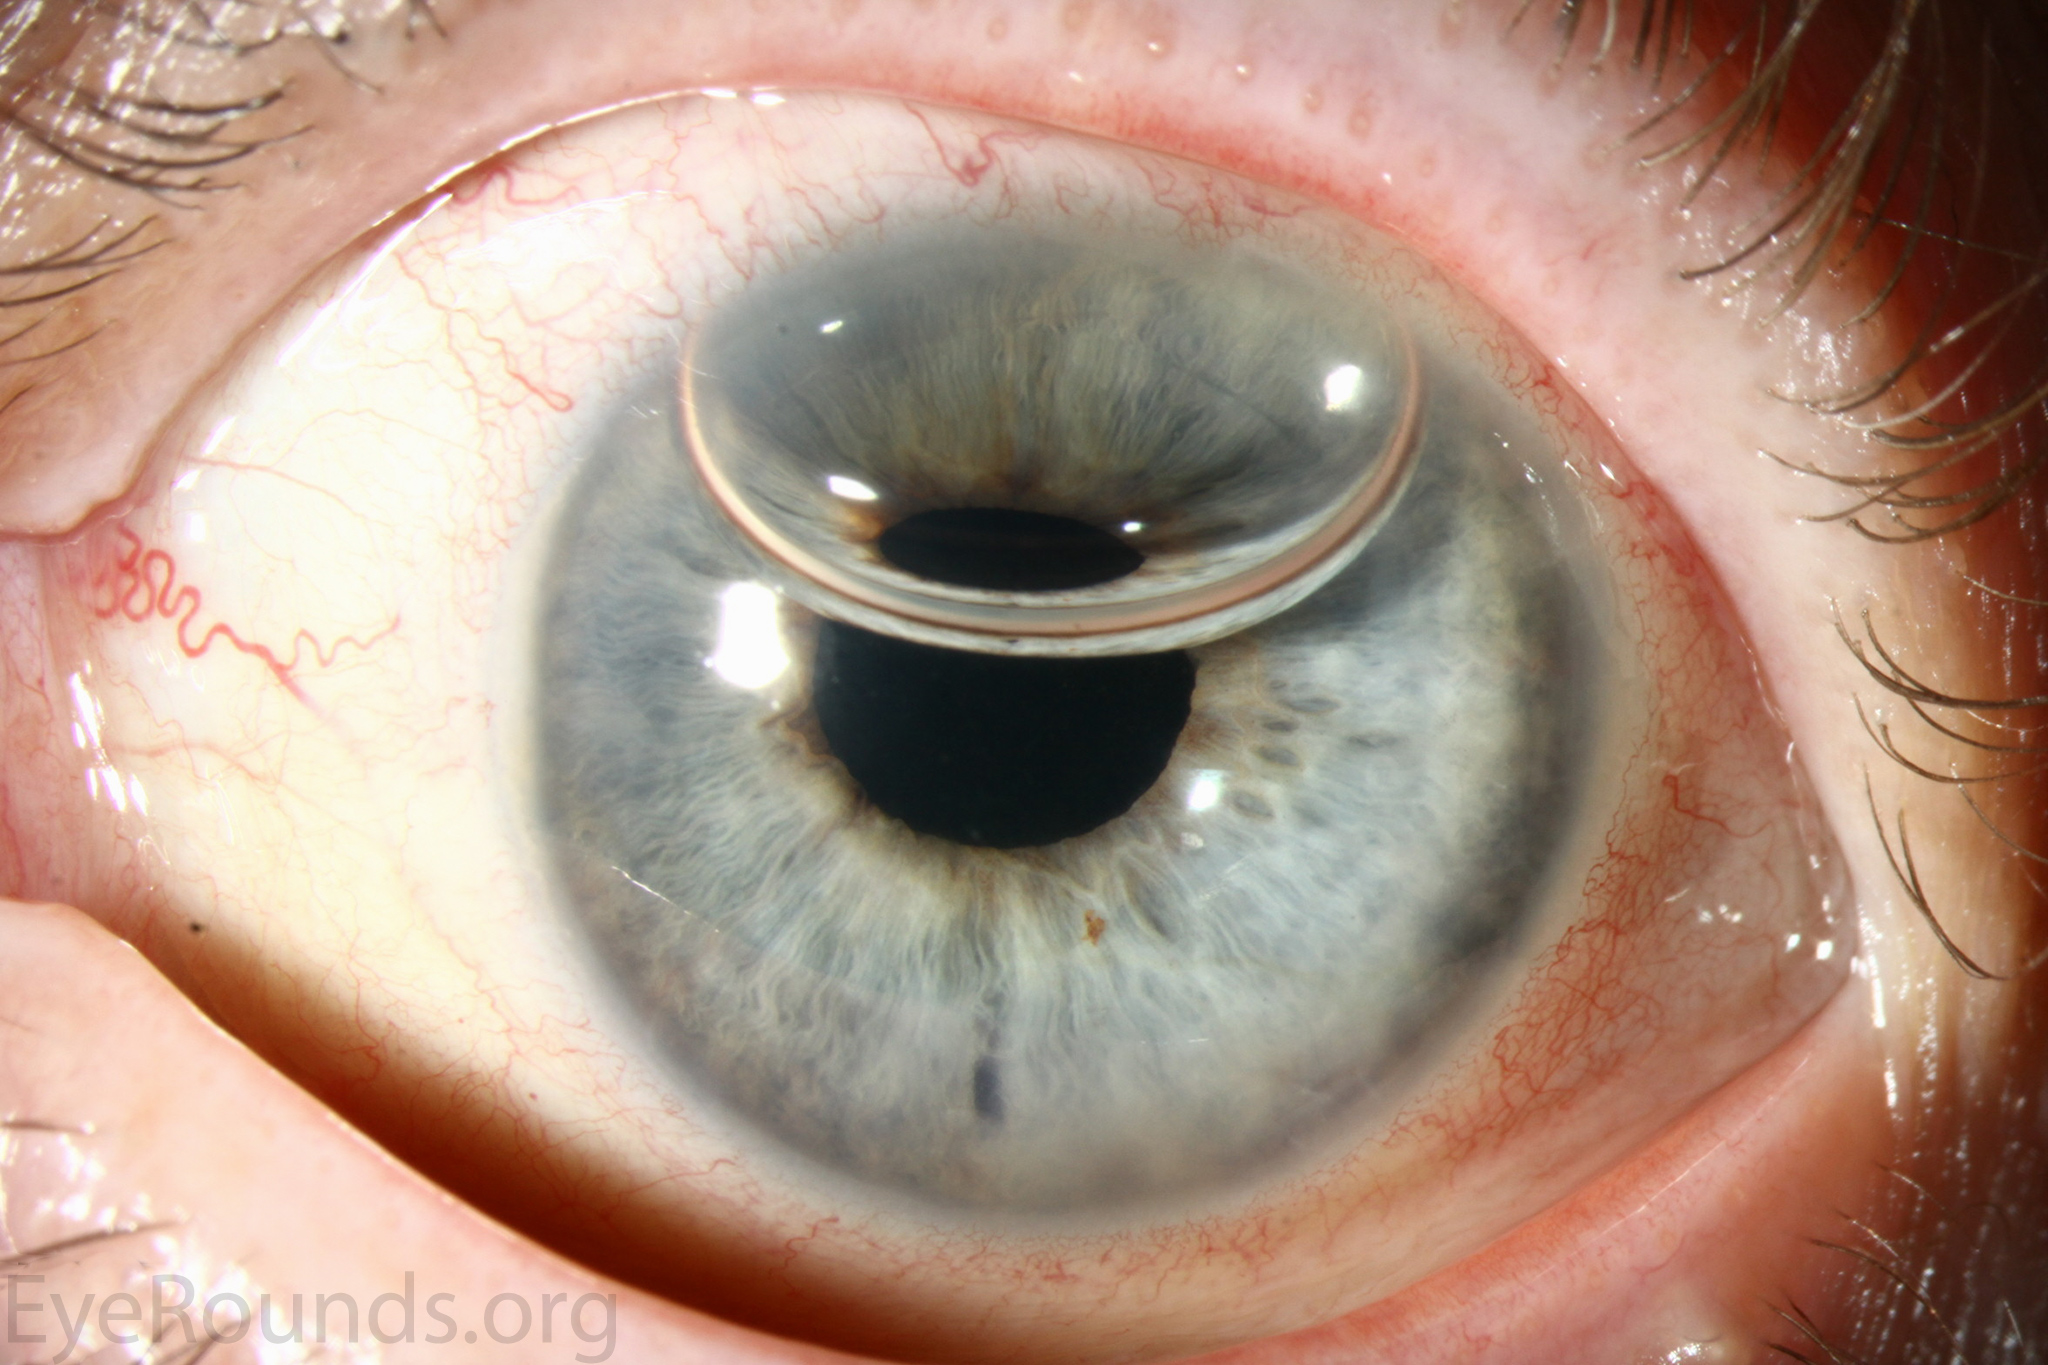

Keratoprosthesis, the transplantation of an artificial cornea, was first performed in Italy by Benedetto Strampelli the 1960s (1). Patients requiring repeat corneal transplantation highlighted the need for an alternative to corneal allograft treatment, as graft survival rates drop with each additional procedure. Historical options have included the osteo-odonto-keratoprosthesis (OOKP) and AlphaCor artificial cornea. These have since been largely replaced by the Boston Type I Keratoprosthesis (KPro), which became approved for use by the U.S. Food and Drug Administration in 1992 (1, 13). The device consists of a clear plastic optic and a prosthetic plate that are sandwiched around a donor allograft or the patient's own corneal tissue. The device is then sutured onto the recipient eye to replace a failed graft or the native cornea. Keratoprosthesis surgery is a procedure of last-resort, reserved for patients who are not candidates for other types of keratoplasty.

Keratoprosthesis implantation is a procedure that involves full-thickness removal of the cornea and replacement by an artificial cornea. The Boston Type I Keratoprosthesis is currently the most commonly used keratoprosthesis device in the US. It consists of a clear plastic polymethylmethacrylate (PMMA) optic and back plate sandwiched around a corneal graft and secured with a titanium locking ring (Figure 15). After the device is assembled, a partial-thickness trephination is performed on the host cornea. Full-thickness resection of the patient's cornea is then completed using curved corneal scissors. The keratoprosthesis is then secured to host tissue using interrupted or running sutures. Generally, patients who have a history of multiple failed PKs are candidates for a keratoprosthesis transplant. Other indications include severe keratitis or ocular surface disease resulting from limbal stem cell failure, such as Stevens-Johnson syndrome (Figure 16), ocular cicatricial pemphigoid, aniridia (Figure 17) and chemical injury (1, 13). The Boston Type II Keratoprosthesis is a similar device with a longer optic designed to extend through an opening made in the upper eyelid (Figure 19). It is indicated for the most severe cicatrizing ocular surface diseases.

KPro placement offers relatively fast visual rehabilitation. The devices are amenable for use in many situations in which other types of keratoplasty are not an option.

There is significant long-term risk of complications for those with a keratoprosthesis. Because the KPro is a foreign body, there is risk of infection or extrusion of the device. Post-operative glaucoma is common and intraocular pressure is difficult to evaluate as the hard optic makes traditional tonometry impossible. For this reason, glaucoma tube shunts are typically placed at the time of the corneal transplant at the University of Iowa. The Diaton is currently the preferred way to measure intraocular pressure in these patients in our institution. Patients can form retroprosthetic membranes requiring treatment with a Nd:YAG laser or surgical membranectomy (21).